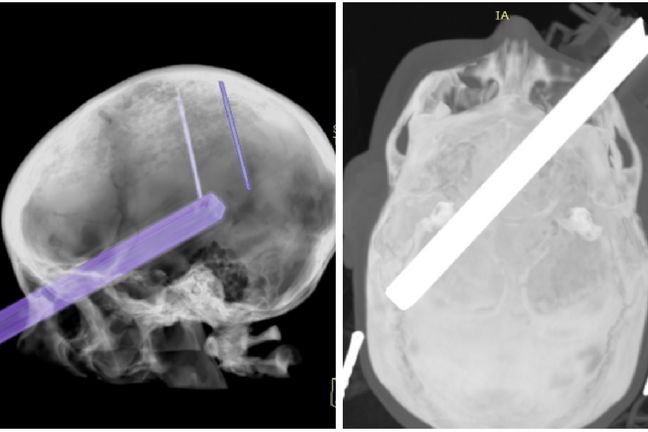

Wynik badania TK Zofii Zwolińskiej w dniu wypadku Wynik badania TK Zofii Zwolińskiej w dniu wypadku

Źródło zdjęć: © Archwium prywatne

Natychmiast wezwano pogotowie, które przetransportowało dziewczynę do szpitala. Wykonano badanie tomograficzne głowy, które uwidoczniło wymiar tragedii: metalowy trzonek od szczotki wbił się w oko, złamał kość oczodołu i umiejscowił na długości 19 cm w mózgu.

Wynik badania TK Zofii Zwolińskiej w dniu wypadku

Wynik badania TK Zofii Zwolińskiej w dniu wypadku © Archiwum prywatne